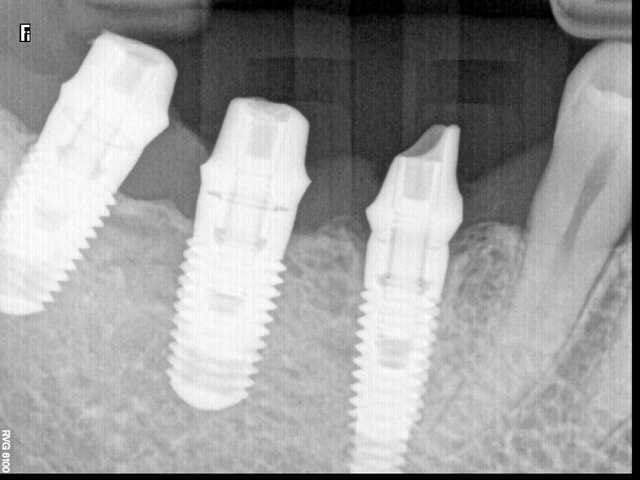

TSV Zimmer....;-)

pas très difficile....et sûr à 100%

je dirais même que sur la prémo tu dois avoir un 3.7/13 ou 16 et les 2 molaires doivent être des 4.7/10 ou 11.5